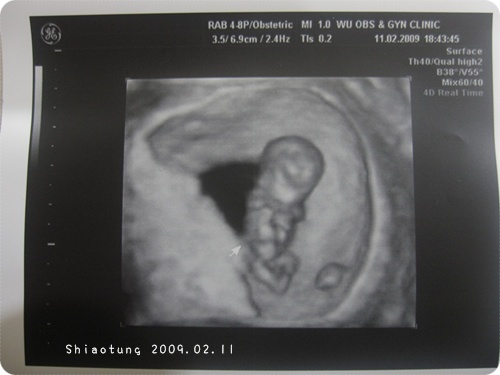

懷孕週數:9

胎兒大小(頭至屁股):約3.01cm →醫生都不會量腿,因為腿哪裡會伸直?

9週熊熊看到就是人型了也!

手腳已經很明顯,

超音波影片裡還不停的揮動...